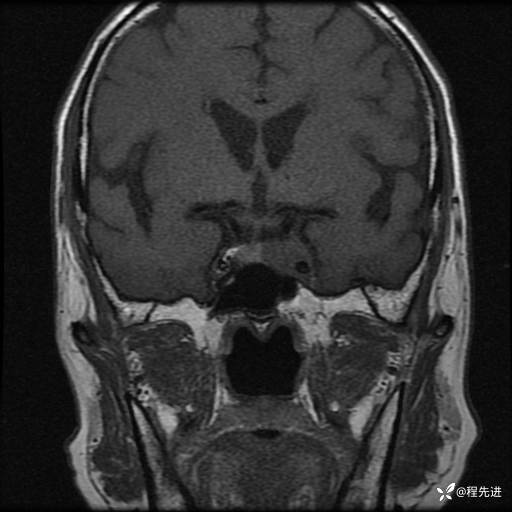

患者性别:男

患者年龄:74岁

简要病史:出现视物重影2月余,未予重视,2月来症状逐渐加重

MRI平扫+增强:

T2: